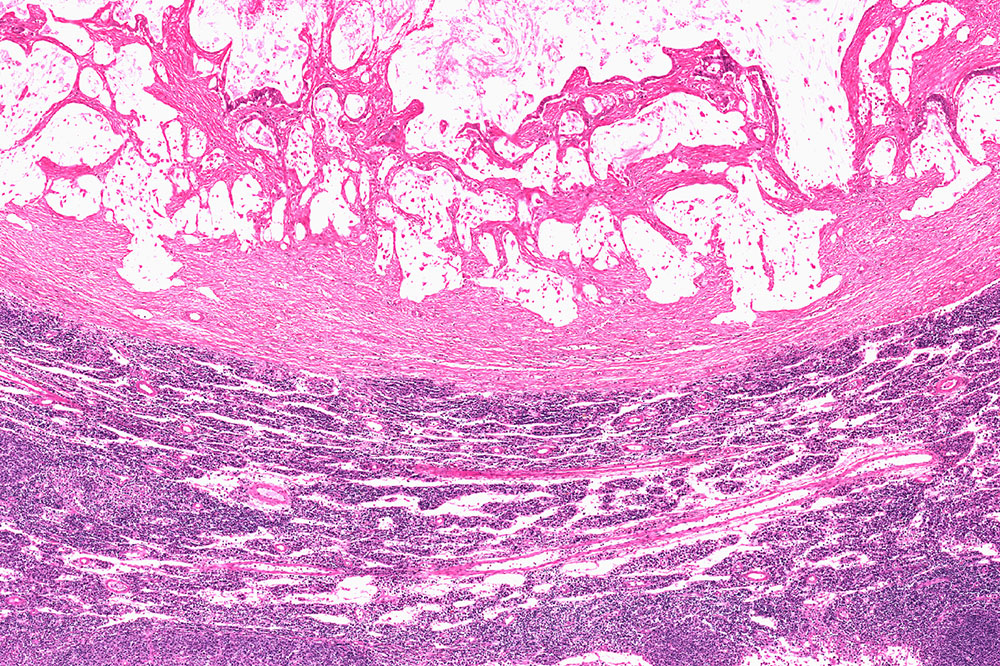

The condition, characterized by a malignant tumor, begins in the nerve cells of the digestive system. With time, they mutate and affect the normal functioning of the cells in the organ. Patients experience symptoms like anemia, abdominal pain, and vomiting, and these further aggravate if the condition is not treated. Therefore, ensure that you consult your doctor at the earliest.